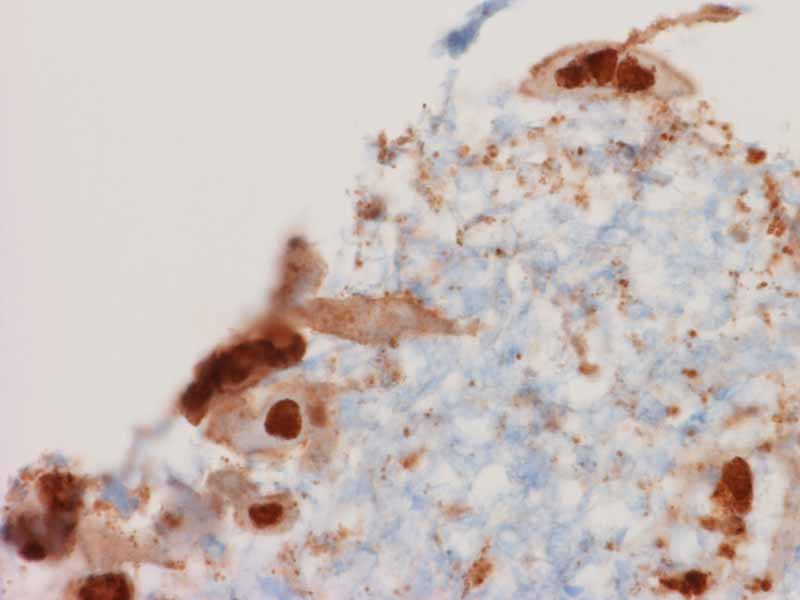

Immunohistochemistry

Immunohistochemistry for HSV: Immunohistochemistry can help to detect some of the viral inclusion that would be difficult to be diagnosed by morphology. It provides good confirmation for the diagnosis.